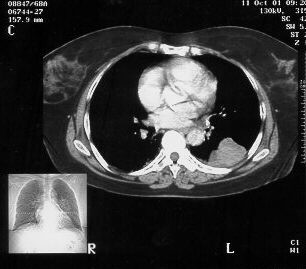

Chest CT demonstrating the 10.0cm x 6.0cm mass in Left lower lobe, apical segment, with pleural involvement.